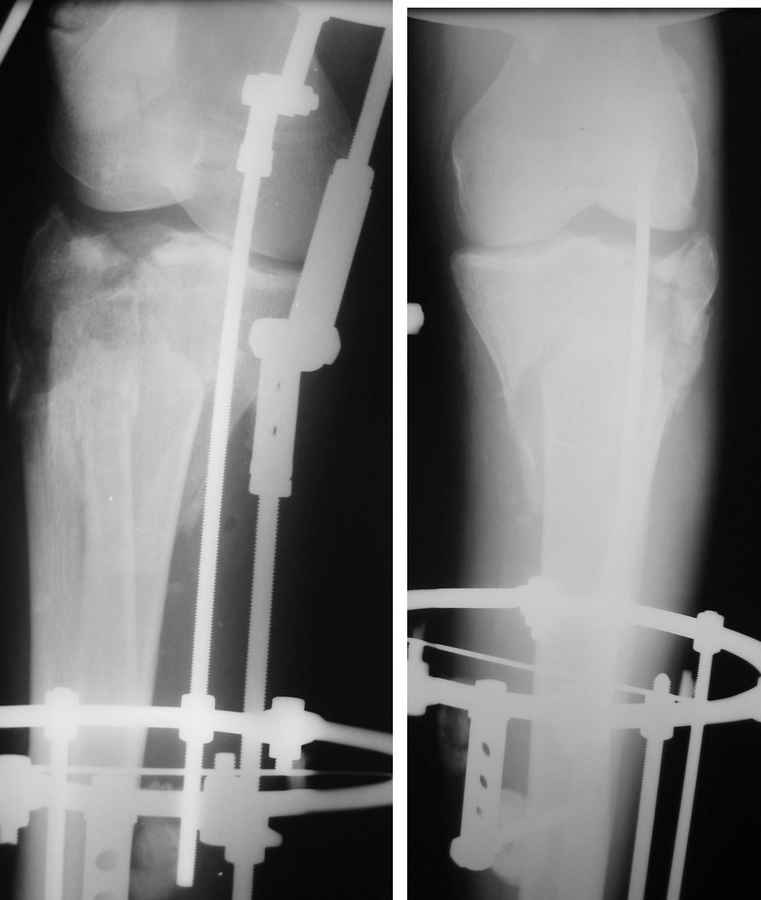

Очаг некроза 4 на 5 см по передней поверхности голени не оставил никакого варианта кроме внешнего остеосинтеза.

Но решили делать в 2 этапа. Первый - восстановить ось и дать костной крошке в проксимальном отделе консолидироваться.

Второй - собственно артродез.

Но по результатам первого этапа думаем дать пациенту попользоваться ногой. А там посмотрим.

Для первого этапа достаточно. Через 5-10 дней мы бы приступили к следующему этапу. А именно, фиксация из ограниченного заднемедиального доступа 1\3 трубчатой или рекон пластиной медиального фрагмента, и остеосинтез наружного мыщелка из второго тоже ограниченного латерального доступа без артротомии, под контролем ЭОПа..... Сухой некроз в данном случае не являлся бы серьезной помехой для внутренней фиксации (во всяком случае, судя по имеющимся фото)

P.S. безусловно, с двумя пластинами LCP, каннюлироваными винтами, хроносом все это дорого... Но того же анатомического и функционального результата можно достичь, используя вместо пластин аппарат Илизарова, и разрезы для репозиции тогда нудны совсем маленькие .